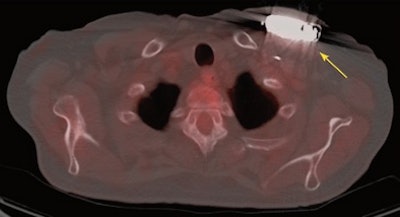

Upon review of the images in group A, 32 (76%) of the 42 patients with suspected CIED infection exhibited positive FDG-PET/CT results. Abnormal FDG uptake around the device generators was seen in 18 patients (43%), and 18 individuals also had uptake over the leads. Thirteen patients (31%) had abnormal uptake in the superficial skin tissue, 13 in the subcutaneous tissue, and two (5%) within the heart.

| Fused PET/CT image shows abnormal FDG uptake (yellow arrow) posterior to the IED generator and compatible with infection. Image courtesy of JACC. |

In Group B, the 12 patients showed no uptake or mild FDG uptake only at the level of the connector. There also was no abnormal FDG uptake among the 12 patients in Group C.